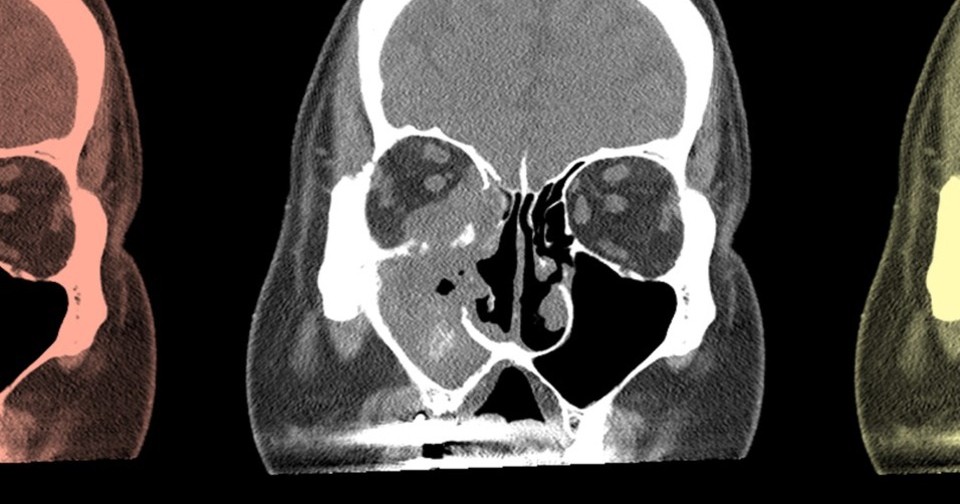

Острый инвазивный грибковый риносинусит считается потенциально опасным для жизни заболеванием, которое часто возникает у пациентов с иммунодефицитами. Инфекция развивается из-за инфильтрации слизистой оболочки носа и околоносовых пазух грибковыми организмами родов Aspergillus, Candida и Mucor и приводит к повреждению тканей, некрозу, а в тяжелых случаях — к распространению инфекции в другие органы.

Частота возникновения грибкового риносинусита варьируется в зависимости от анализируемой популяции и основных факторов риска: разброс составляет от 0,11 до 7,7 случая на миллион человек в год. Однако эпидемиология этого состояния с течением времени остается малоизученной.

Общая распространенность случаев грибкового риносинусита у пациентов с ослабленным иммунитетом составила 11,8 процента. Причем в последние года она заметно возросла: до 2013 года она оценивалась в 9,1 процента, а после — в 16,6 процента. Общий уровень смертности составил 31,2 процента, и с течением времени она снижалась. Так, до 2013 года смертность была заметно выше и достигала 41,9 процента, а после 2013 года она снизилась до 28,2 процента. Также анализ показал, что общий уровень осложнений грибкового риносинусита составил 37 процентов без значительной разницы между периодами исследования.